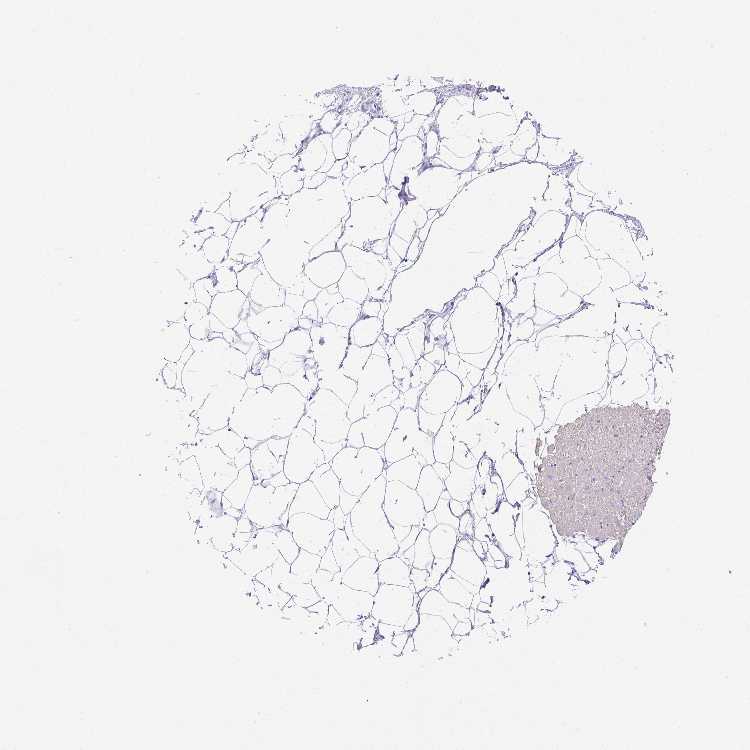

HEART MUSCLE - Antibody stainingi

Antibody staining in the annotated cell types in the current human tissue is reported as not detected, low, medium, or high, based on conventional immunohistochemistry profiling in selected tissues. This score is based on the combination of the staining intensity and fraction of stained cells.

Each image is clickable and will lead to virtual microscopy that enables deeper exploration of all samples and also displays staining intensity scores, fraction scores and subcellular localization as well as patient and tissue information for each sample.

Antibody HPA058448

Cardiomyocytes Low